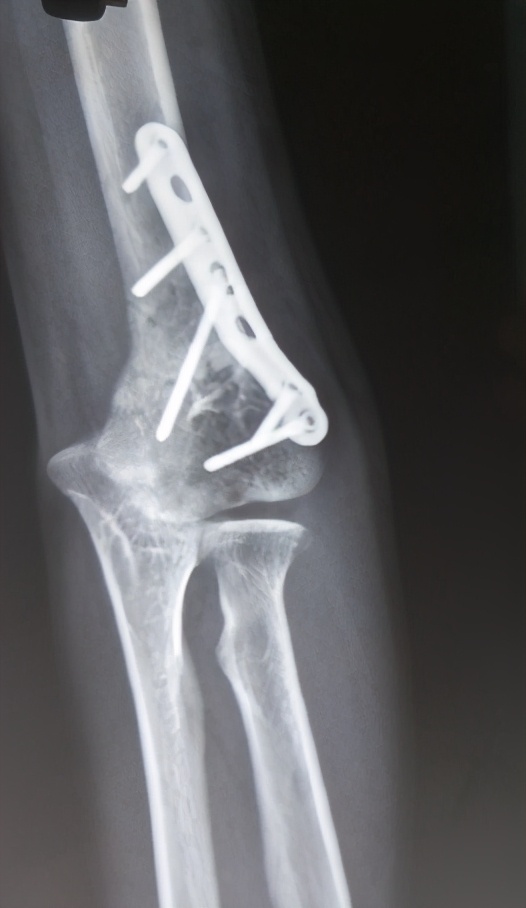

近日,她前往上海市第六人民医院就医,骨科-修复重建科文根副主任医师详细问诊,认真分析影像学资料,明确患者左上肢内翻畸形,予以肱骨髁上楔形截骨矫正术。术后上肢力线恢复正常,李小姐非常满意。

肘内翻不会随着生长发育而改善,肘内翻的畸形应尽早就医。手术有多种方式,最基本的都是要通过肱骨髁上截骨,外侧闭合性楔形截骨是最安全、最容易的,并最具内在稳定的截骨方法。

根据患者年龄及畸形程度确定固定方式,对于年幼患儿可采用螺钉及克氏针联合固定,而钢板及螺钉固定主要适用于青少年。